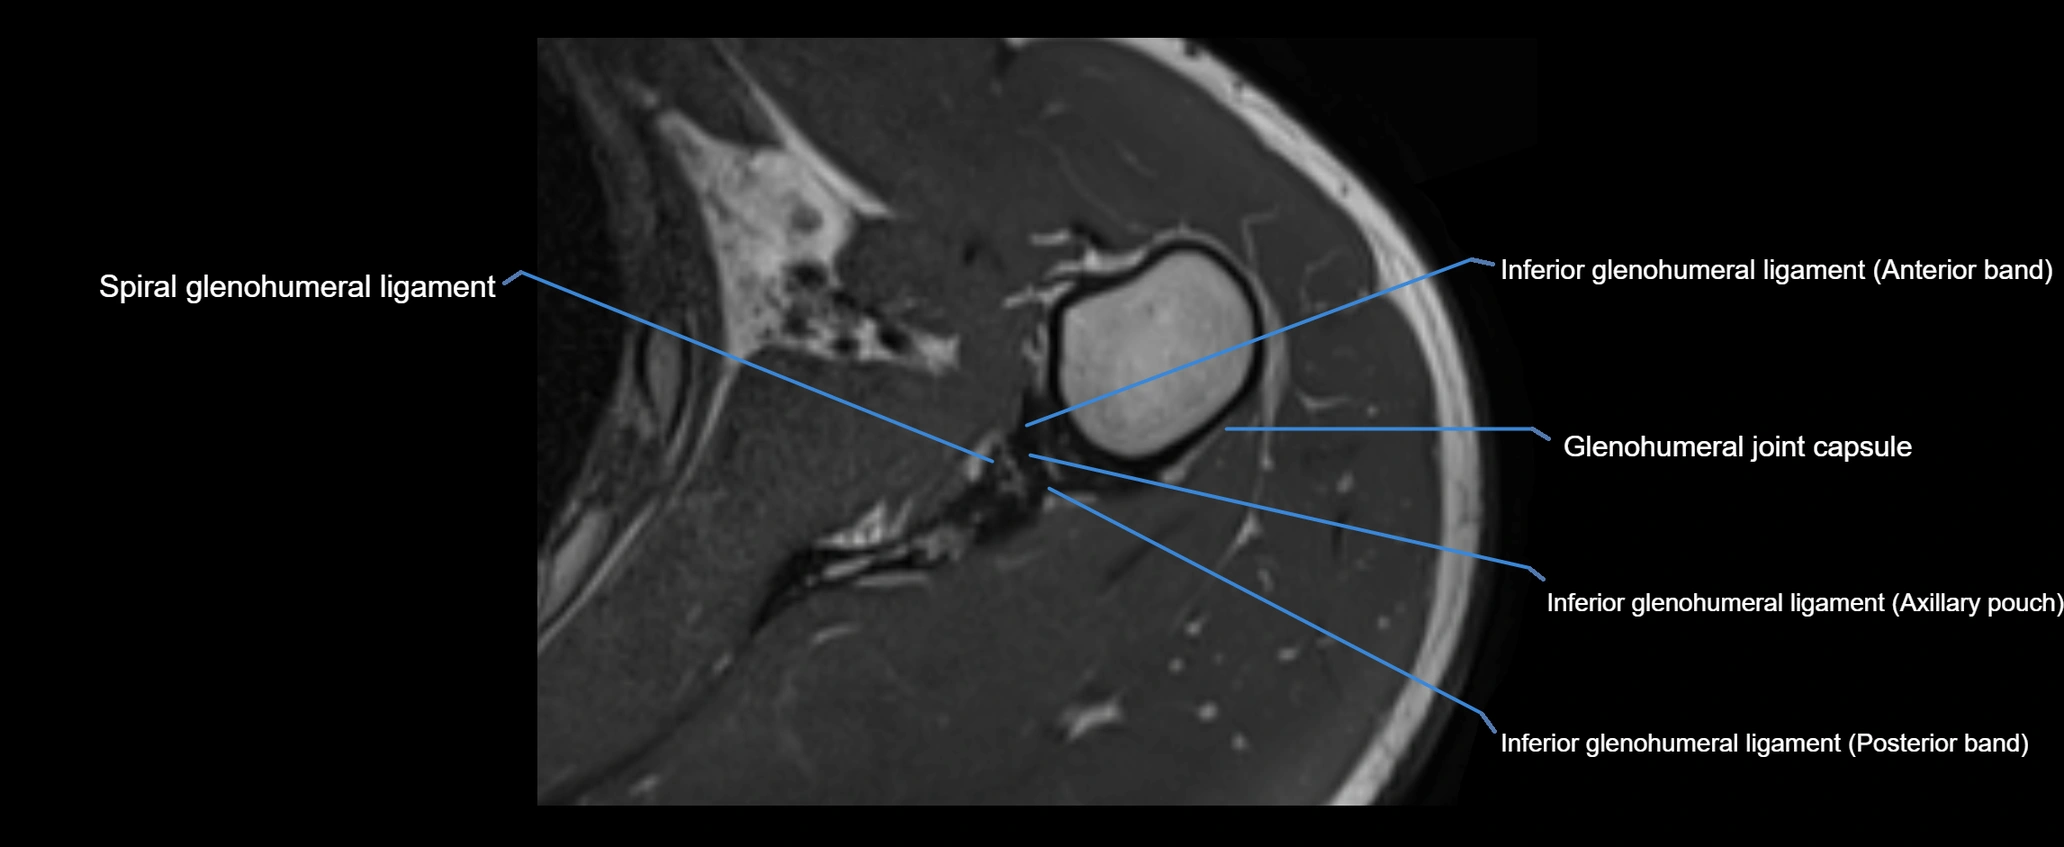

MRI images

image